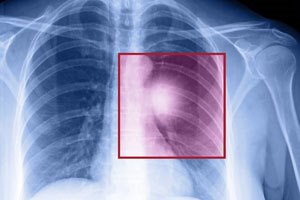

סרטן ריאות: בדיקה גורלית

טור אישי מרגש: רוני שרון מעולם לא עישנה - וחלתה בסרט...

מאת: ~~רוני שרון~~ 08/09/2015